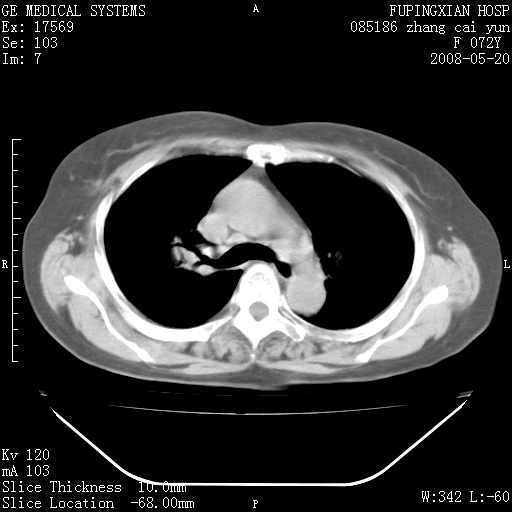

标题: CT13542:发热,咳嗽数日,经抗菌素治疗好转,请大家看排除 [打印本页]

标题: CT13542:发热,咳嗽数日,经抗菌素治疗好转,请大家看排除

右上叶支气管走行自然,未见明显管壁增厚等征像,另左主支气管起始部可见异常腔道向左侧延展左肺动脉干后方,与左下叶支气管相通,为左下叶支气管变异?

有节段性阻塞性肺炎与不张,近段支气管狭窄,周围散在肿大淋巴结影,以周围型肺癌可能性大,建议纤支镜检查。

右肺上叶实变影,内见支气管充气征,右上叶支气管通畅,肺门区未见软组织密度影,抗炎治疗有效,考虑炎症,建议继续抗炎治疗复查。

右上肺实变,间内有支气管充气征,考虑炎症,建议抗炎后复查